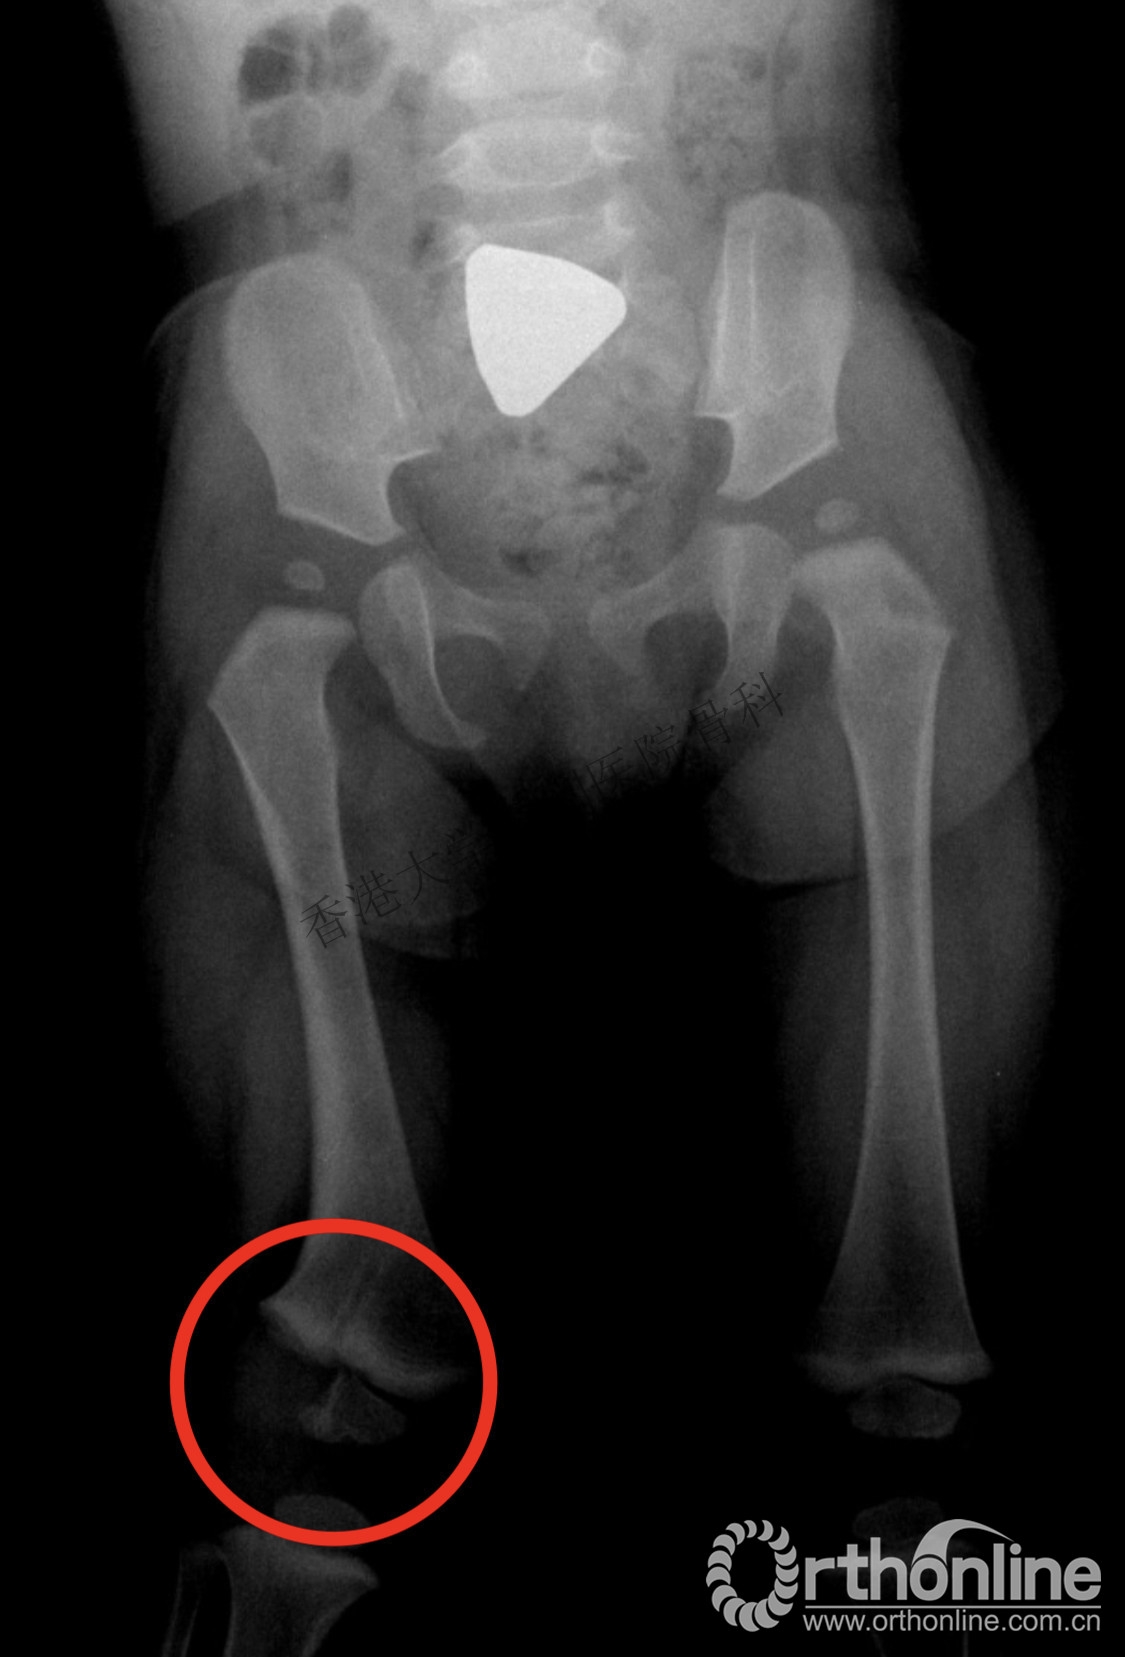

6岁成骨不全患儿,1岁开始反复骨折,容易被误诊为虐待伤。

双下肢截骨矫形内固定术后,畸形得到良好纠正。

2. 虐待伤常发生在婴儿(1岁以内),而大约90%小于6个月,近一半的股骨干骨折发生在会走路之前,大都是非意外伤。

虐待伤无特异的骨折类型,需考虑患者的年龄,损伤的类型、所述的损伤机制以及有关的心理社会因素等。

当遇到拐角部骨折,尤其是股骨远端骨折和多发性肋骨骨折、颅骨骨折或具有不同愈合阶段的多发骨折时要高度怀疑非意外伤。

有时,成骨不全可能会被误诊为虐待伤,让父母担心把孩子送到医院会引起误解,从而延误诊治,导致反复骨折,陷入恶性循环。因此,正确的诊断和适当的治疗显得尤为重要。